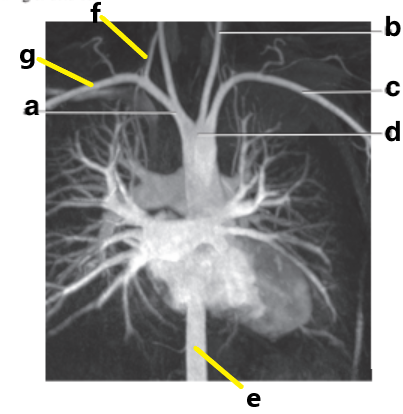

Which letter is the Left common carotid ?

b

Which letter is the left subclavian artery ?

Which letter is the Right common carotid artery ?

d

What is letter a ?

Brachiocephalic trunk

Which letter is the Right vertebral artery ?

f

c

Which letter is the right subclavian artery ?

g

a

Which letter is the brachiocephalic trunk ?